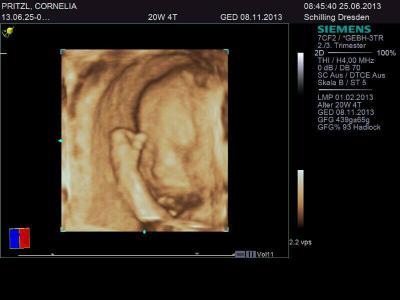

Guten Morgen Feindiagnostik gestern war alles super! ca.25cm und 400g und ein kleiner süßer Junge! Muss zugeben ,ich hatte mir ein Mädchen gewünscht und war nur mäßig erfreut.Nun hab ich mich schon etwas mit dem Gedanken angefreundet.Der Kleine kann ja nix dafür.Süß sieht er schonmal aus..Ich halte mich jetzt mit Süßkram etwas zurück damit er nicht sooo groß und schwer wird...Meine anderen Jungs waren ziemlich groß und schwer! Mit 53cm und 54cm und um die 3900g schwer an der Grenze..Lauft Fa soll ich mich eher auf gesunde Nahrung konzentrieren auch um einer weiteren Schangerschaftsdiabetes vorzubeugen.

Bild zu Feindiagnostik - Forum für November - Mamis